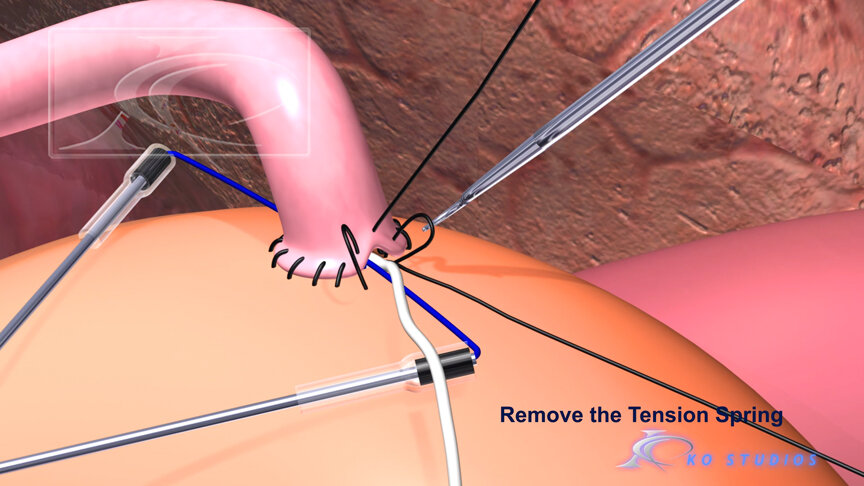

EnCompass F2 Device for cerebral embolic protection system in TAVR procedures

EnCompass Technologies

EnCompass’ F2 filter has pores small enough to block most emboli to the brain while preserving blood flow. During the TAVR procedure, 360-degree wall apposition of the filter in the aortic arch prevents migration. The filter, attached to a self-expanding, nitinol stent, is easy to insert, deploy and retrieve, according to the company. Copyright ©2021 KO Studios.